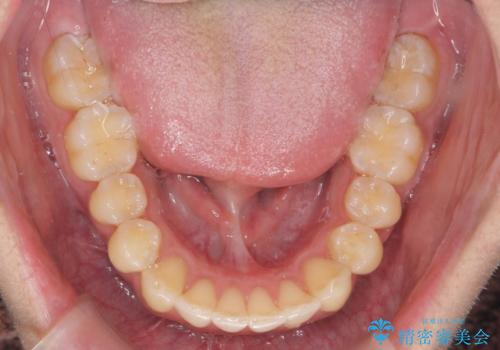

過蓋咬合・上顎前突・叢生を改善するマウスピース矯正

・前歯の深い噛み合わせ (過蓋咬合)

・上顎前突(Angle Class2)

・叢生(がたつき)

以上のような問題点をマウスピース矯正インビザラインとマイクロインプラントを用いて矯正治療を行い改善して行きます。

20時間以上のマウスピース装着、ゴムかけを遵守していただいたおかげでしっかりと噛み合わせ、がたつきの改善を行うことができました。